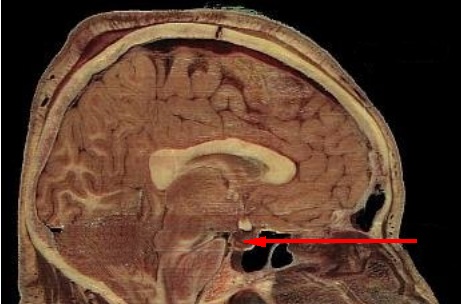

Se trata de una glándula compleja ubicada en un espacio óseo conocido como silla turca del hueso efenoides. Este espacio está situado en la base del cráneo, concretamente en la fosa cerebral medial, la cual conecta el hipotálamo con el tallo pituitario o tallo hipofisario.

Localización

La hipófisis es una glándula compleja que se aloja en un espacio óseo que se llama silla turca del hueso esfenoides. Esta región está situada en la base del cráneo, ocupando una zona conocida como fosa cerebral media.

La fosa cerebral media es la región del organismo que conecta el hipotálamo con el tallo pituitario. Posee una forma ovalada, y un diámetro antero-posterior de 8 milímetros, transversal de 12 milímetros y vertical de 6 milímetros.